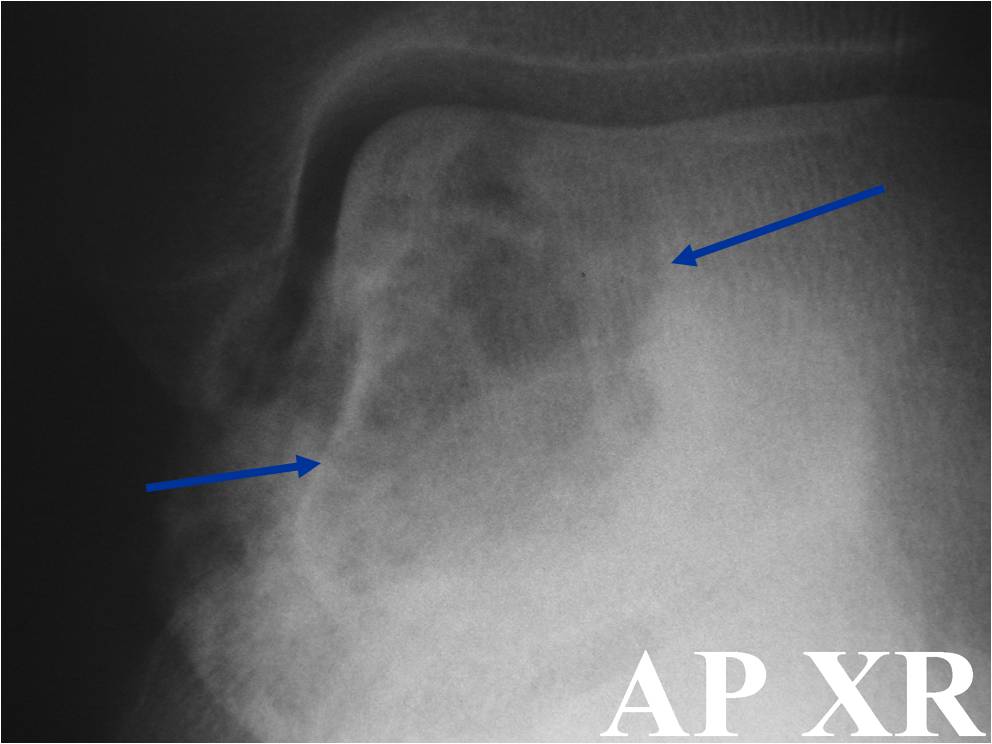

Radiographic Presentation

- Presents as a highly defined/well circumscribed geographic oval/round lytic defect

- Surrounded by rim of sclerotic bone

- Usually in epiphyseal region

- Lesion ranges from 3 cm to 6 cm diameter

- Usually radiolucent

- May have fine trabeculae and irregular calcifications

- Calcifications are often better detected with a CT scan but are not uniformly present

- Lesions may expand the bone and new periosteal bone may form

- Bony end plate, cortex, bone contour are unaffected

- (Plain x-ray appearance)

- Geographic lytic lesion IA/IB margin of sclerosis

- Usually Eccentric more often than Central in the bone

- Rarely expansile (rarely penetrates the cortex)

- Calcified chondroid matrix 30%-50% of cases

- Often better detected with a CT Scan

- Periosteal Reaction 30-50% of cases

- Usually occurs in Adjacent Diaphysis/Metaphysis since epiphysis is intraarticular and not surrounded by periosteum